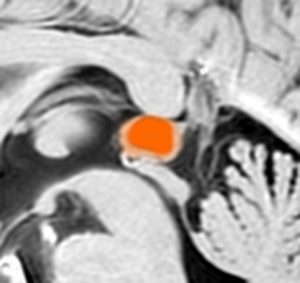

若い女性にできた,症状の全くない松果体のう胞です。右側は拡大図で,8 mmくらいの大きさでしょうか。もちろん何もする必要はありません。たくさん発見されるものです。